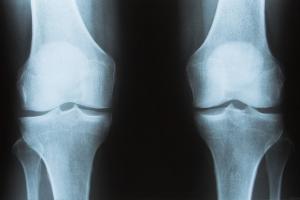

En las mujeres este proceso se agrava con la menopausia, cuando el ovario deja de producir estrógenos, una hormona indispensable para la salud ósea. Así de ser la estructura más solida del cuerpo, el hueso se convierte en una esponja porosa que pierde densidad y se vuelve frágil, la antesala de lo que los médicos llaman osteoporosis.

Las ratas que tomaron maca roja desarrollaron una increíble capacidad para regenerar el hueso, incluso mucho más que el grupo que tomó hormonas. “Con el estradiol los orificios del hueso se hicieron más pequeños y se revirtió la osteoporosis. Sin embargo, con la maca ocurrió lo mismo, incluso en mayor grado. La ventaja es que la maca no daña los tejidos como si lo hace la TRH. Además no es cara y es muy accesible”.